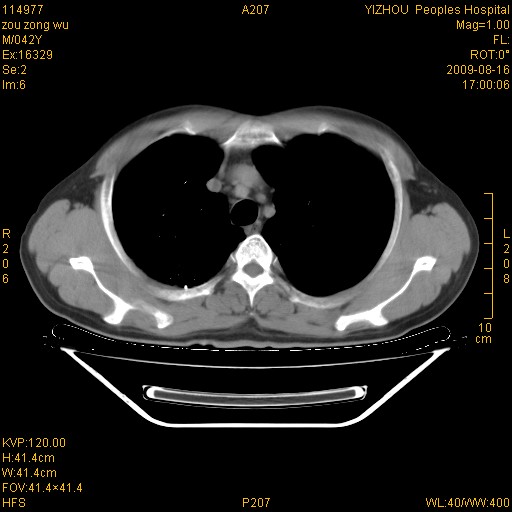

以下是引用zjzjr在2009-8-17 10:42:00的发言:[br]右侧间质性肺炎伴纤维化,右肺下叶肺囊肿伴感染(不除外外伤后引起),右肺野及胸壁软组织\\肝内见多发斑点状,中枪了吧.右侧胸膜肥厚\\粘连.